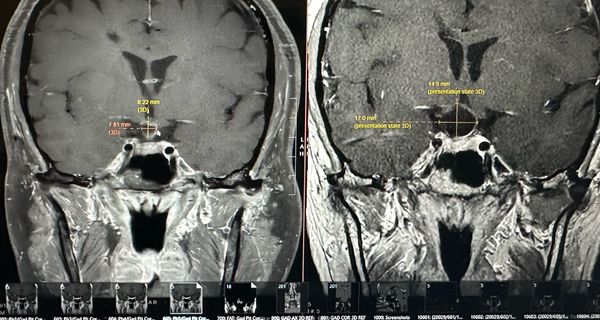

THEY SAID IT’S SHRINKING! THE CHEMO IS WORKING! I am still waiting on my official radiology report but my neuro oncologist measured it on my MRI and he thinks it shrunk 30%. What’s messed up is my mind and body…

Okay, first off, I had my two month MRI yesterday and learned that the tumor shrunk another 30-40% !! Modern medicine, especially precision oncology, is f****** AMAZING. It's crazy to think that exactly two years ago I was being wheeled…

Okay, so the results are in. Still waiting on an official radiology report to confirm but from what my neuro oncologist can see, the tumor has remained very small and inactive. This is GREAT! Huge exhale….. But of course there…